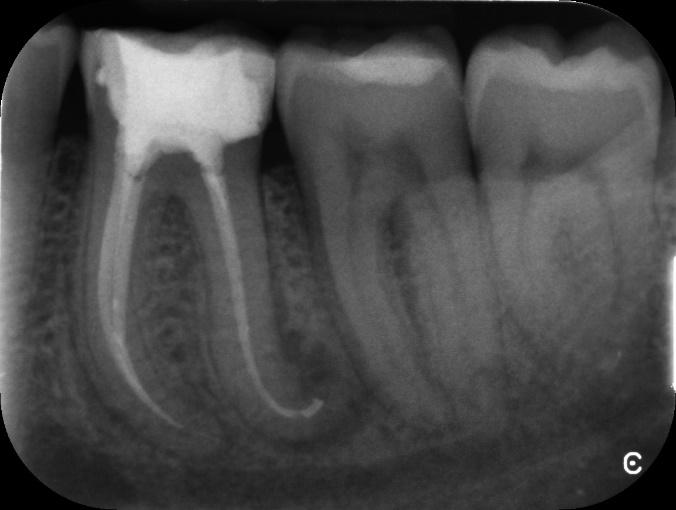

Lower Molar curved root Primary root canal treatment and rebuild